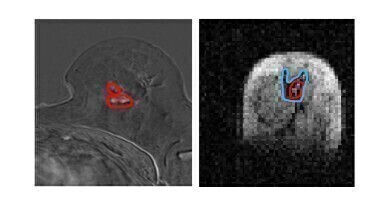

Side by side image of same breast tissue in MRI and FCI. (l) MRI image of breast with cancerous tumours circled in red (r) FCI image of same breast shows same tumour in red with secondary tumour spread in blue. Spread not visible in MRI. The patient had a mixed tumour i.e two different types of tumour and one of them is not visible in MRI. Photo Credit University of Aberdeen -

Photo Credit University of Aberdeen -